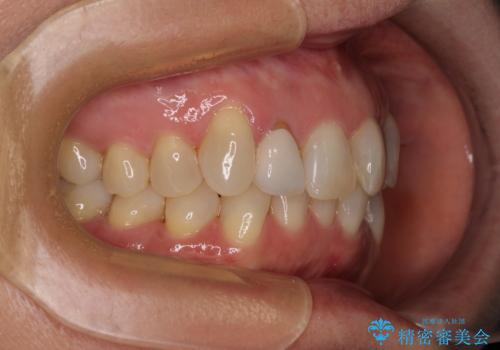

前歯のデコボコとむし歯治療の跡 インビザライン矯正とオールセラミッククラウン治療

- 前歯のセラミッククラウンの縁が見えることが気になってから、デコボコも気になるようになってきたとのことで来院された患者様です。

デコボコの程度は中等度であったため、インビザライン・モデレートパッケージにて歯列を整えることとしました。

セラミッククラウンの装着されていた前歯と、大きな修復治療の跡がある反対側の歯は、矯正治療後に補綴治療を行うこととしました。